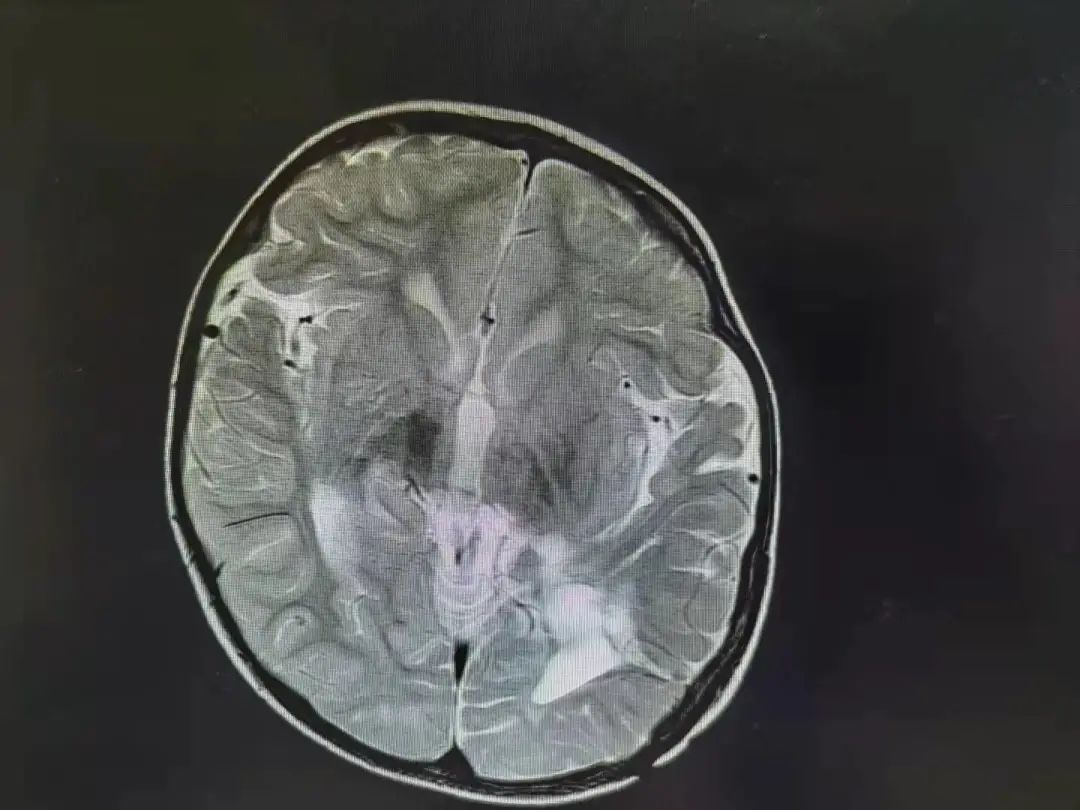

六六手术后脑部影响图 肿瘤已经消